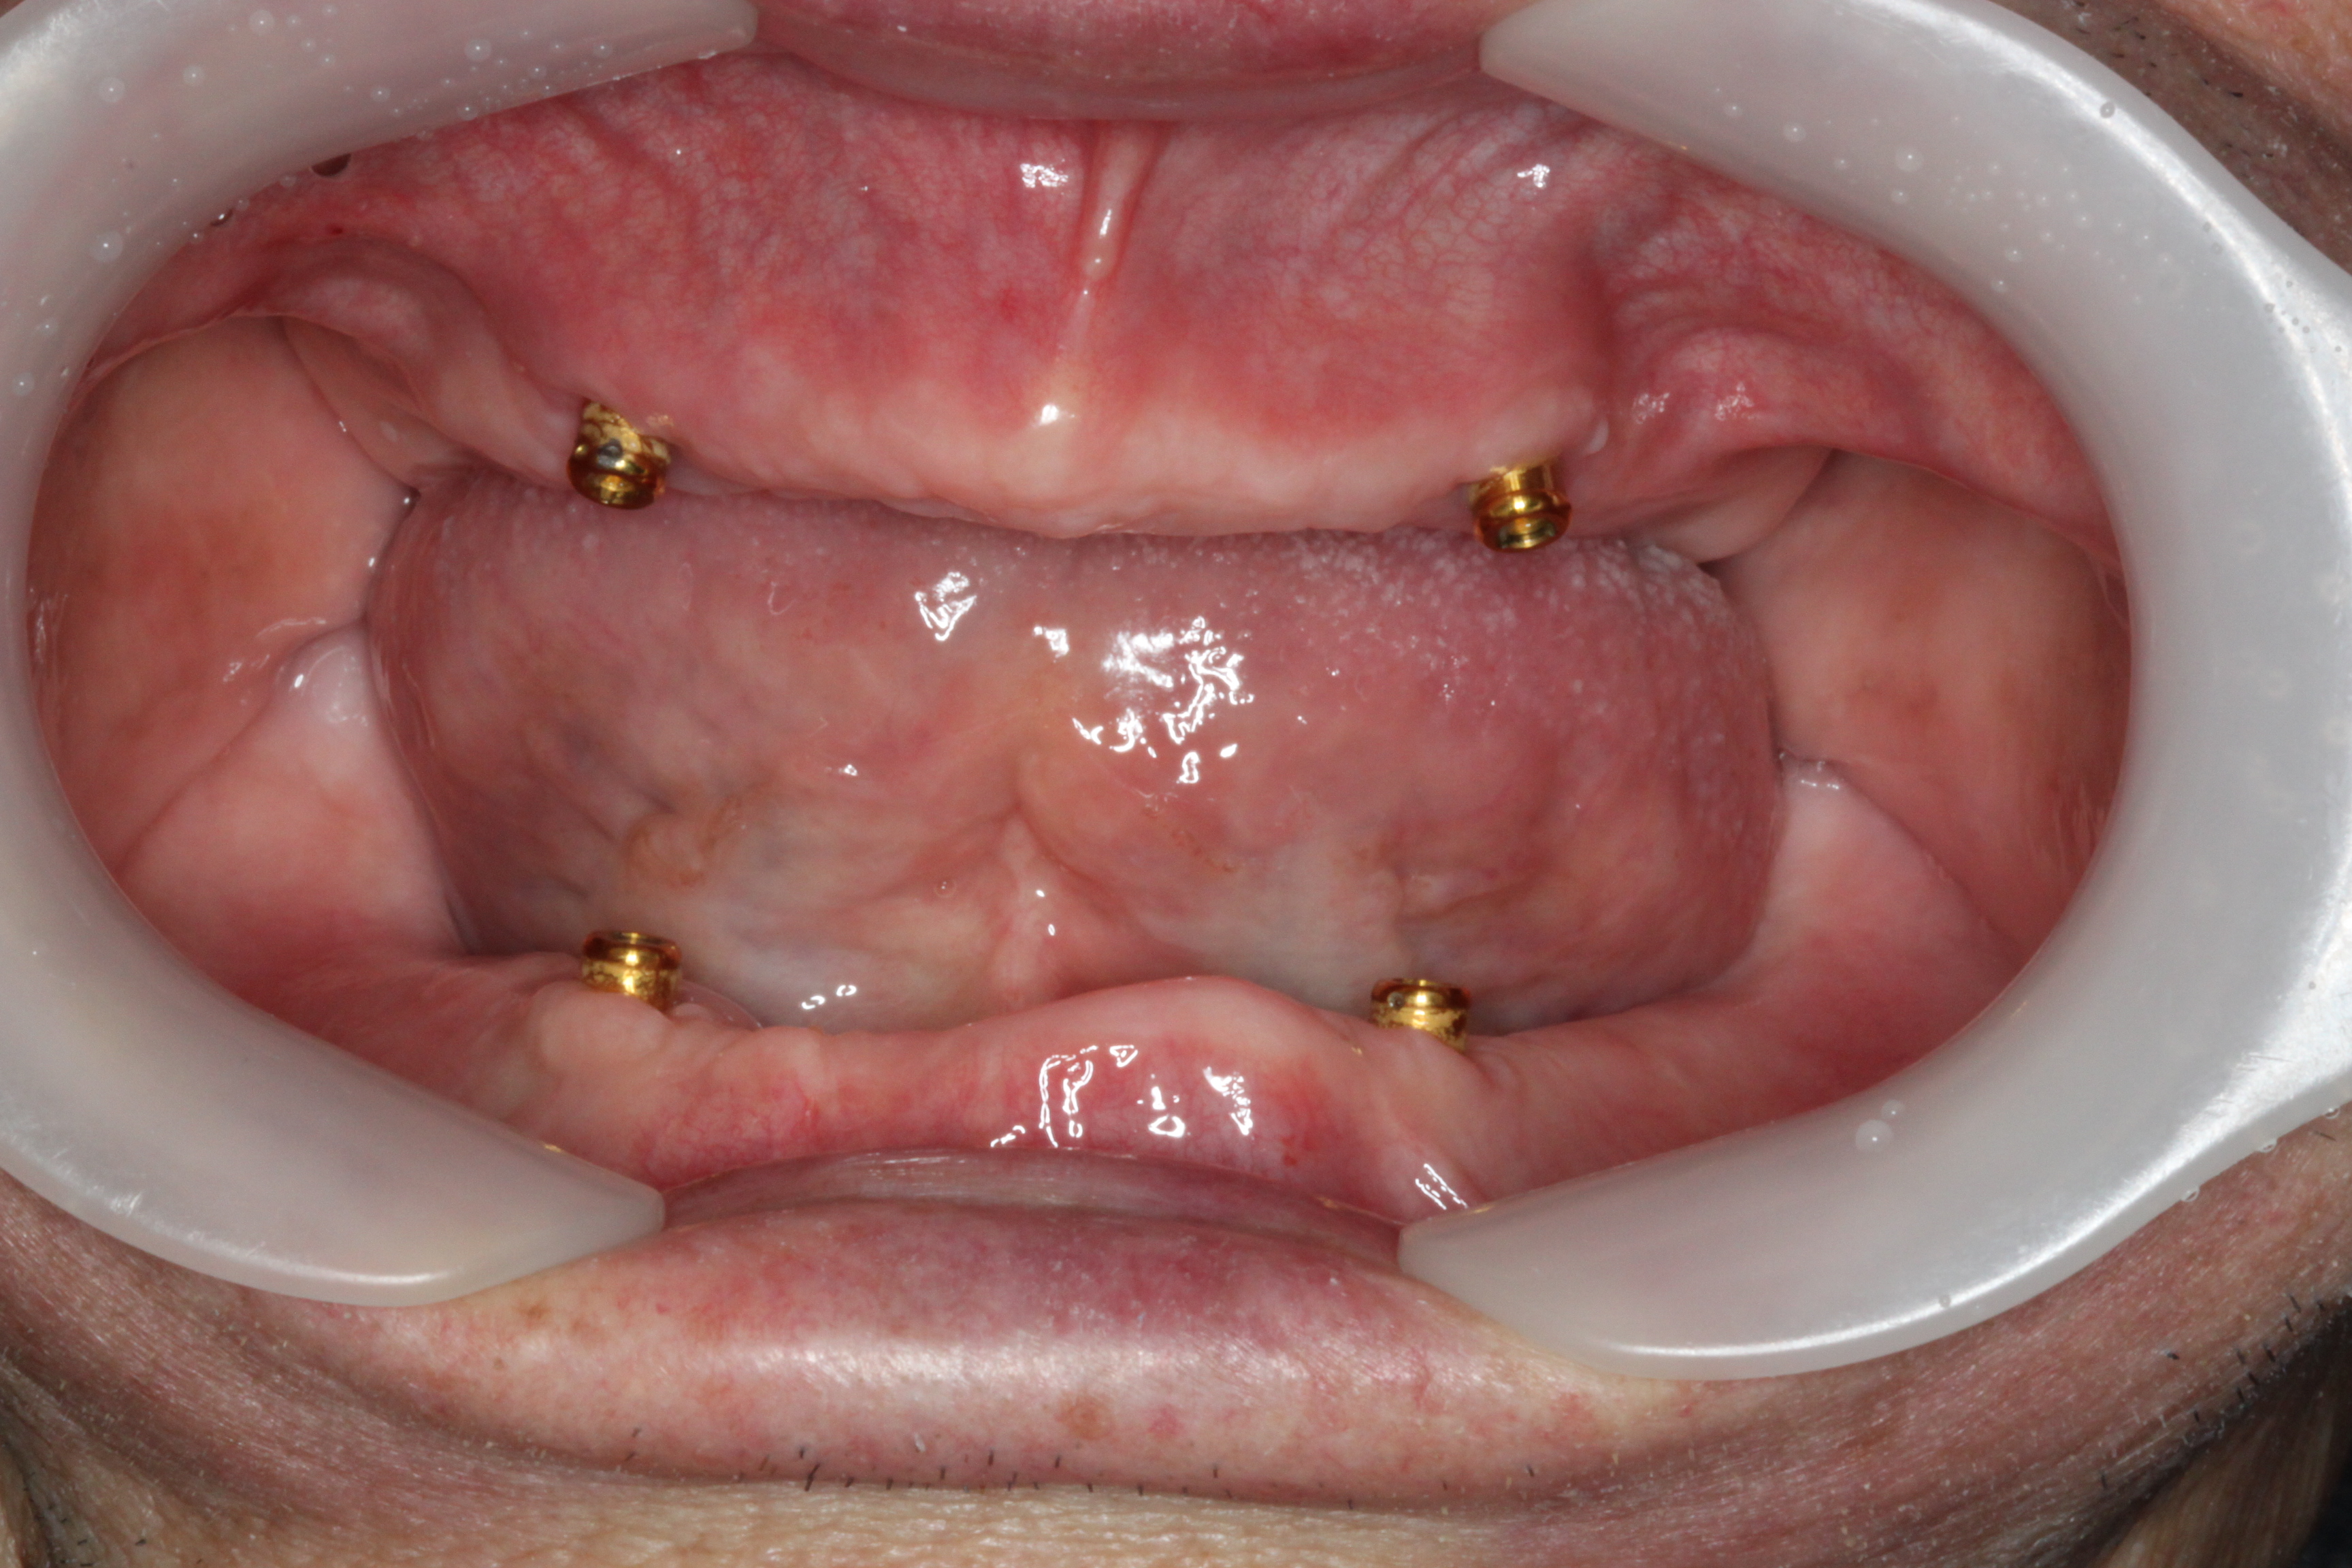

BEFOREAFTERBEFOREAFTER(식립)AFTER(착용)

임플란트 틀니